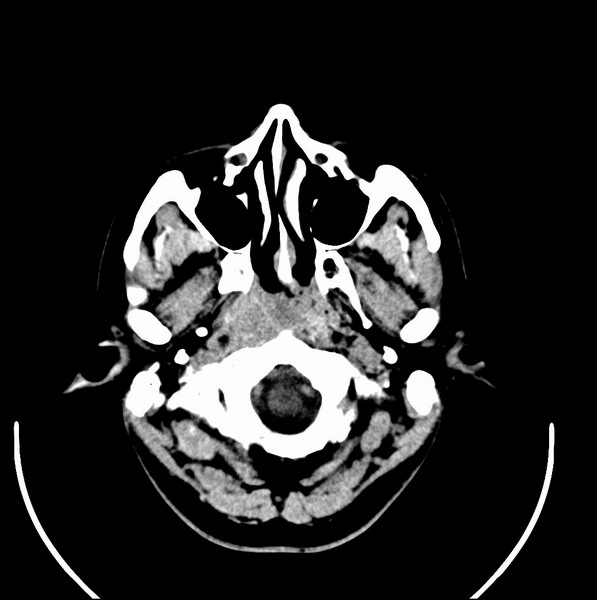

男、30、发现鼻咽部肿瘤侵犯海绵窦,未发现明显淋巴肿。请问国内那家医院治疗鼻咽部肿瘤最好?手术以何种方式为主?病灶可否全部切除?急切期待的大家的帮助。

扫描示鼻咽腔不对称,中度狭窄,右侧咽隐窝消失,局部软组织肿块,鼻咽右侧壁增厚形成肿块,突入鼻咽腔,肿块平扫呈等密度,肿块向深部侵润,右侧翼内外肌受侵,右侧咽旁间隙变窄;向后生长,头长肌界线欠清,向后上生长侵犯同侧颈动脉鞘区。双侧海绵窦增宽,内见软组织影与鼻咽部肿块相连。考虑鼻咽癌。鼻咽癌主要是放射治疗,且效果较好;到当地有治疗设备较大医院治疗即可。

鼻咽部新生物(纤维血管瘤?鼻咽癌?)侵犯右侧中颅窝底及右侧海绵窦;建议必要时活检定性。